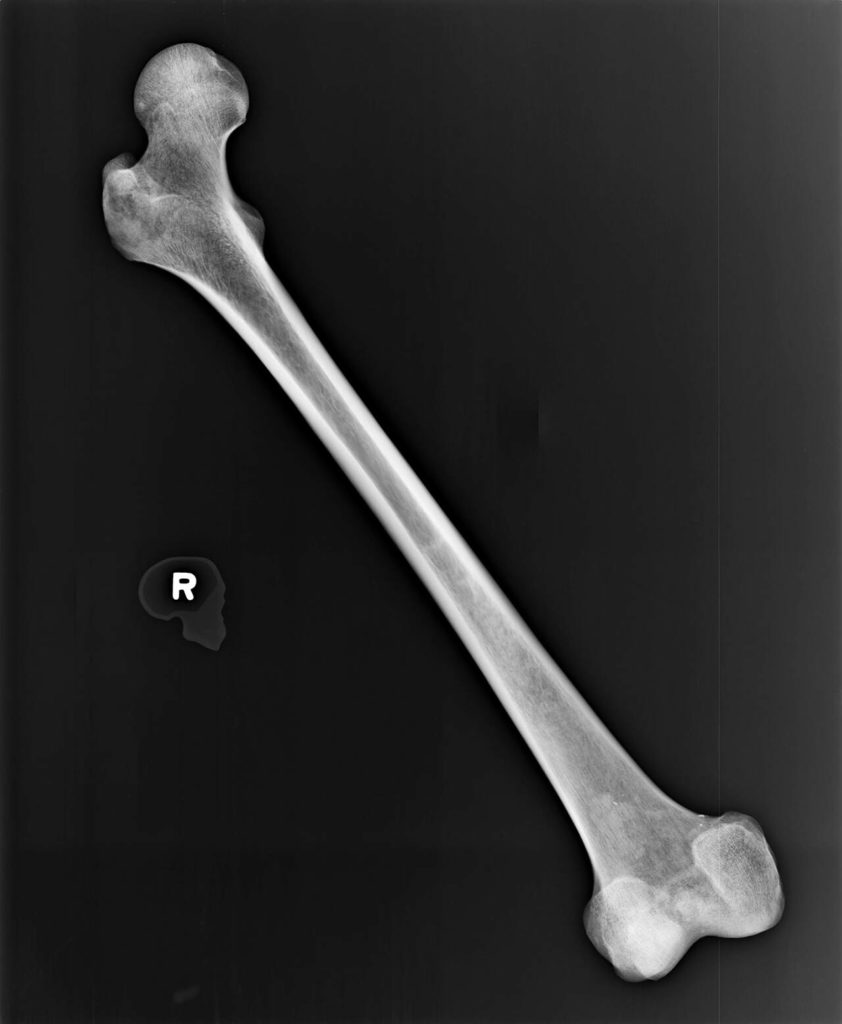

Dr. Kathy Taylor, a state forensic anthropologist, examined the exhumed bones, too. She estimated they belonged to a man with Caucasian ancestry, who stood from 5-foot-2 and and 5-foot-6. She guessed he could be anywhere from 27 to 61 years old. She saw no “perimortem trauma” — that is, trauma at or around the time of death — but she did note an unset left femur fracture that had healed awkwardly. It would’ve left him shuffling around in pain, likely for years, about 2 inches shorter on one side.

A section of the right femur was sent to the University of North Texas to extract DNA and upload it to the FBI’s database, CODIS. Those samples were obtained by March 2019. Death investigators ruled out many possible matches through DNA and dental records, but still they were without a name.

In 2021, another piece of the John Doe’s femur was mailed to Othram, Inc., a private lab specializing in difficult DNA cases. Othram has helped Snohomish County investigators with several other remains cases in the past, extracting genetic profiles to upload to ancestry databases. That way, a genealogist can build the unnamed person’s genetic family tree, find his family and ultimately figure out his name. It’s the same process any amateur sleuth can learn these days to find their own long lost relatives, given enough time and patience.